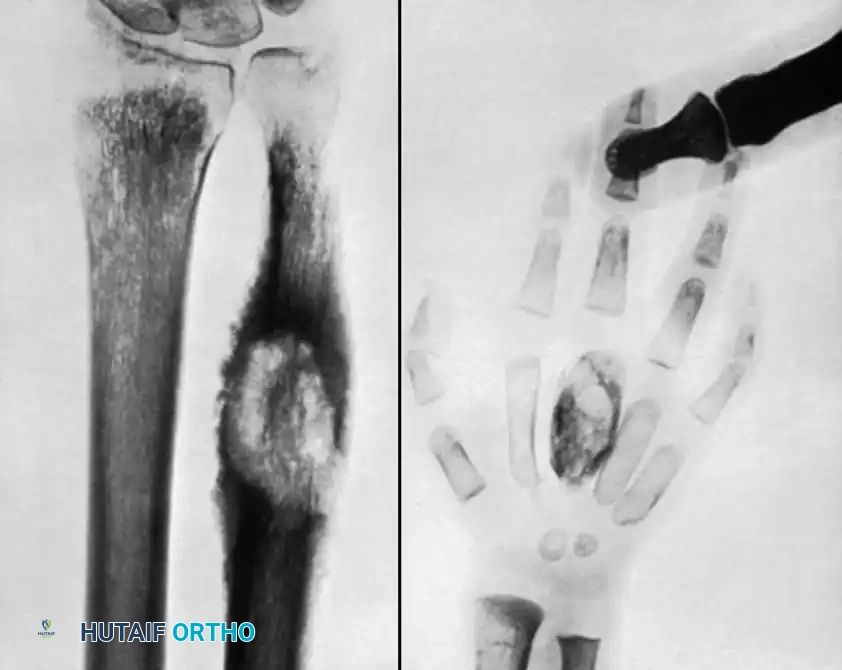

The Wrist and Hand

Tuberculosis of the hand often presents as tuberculous dactylitis (spina ventosa), characterized by a painless, fusiform swelling of a phalanx or metacarpal. The bone expands, and the cortex thins, creating a cystic appearance.

Wrist involvement typically begins as a tenosynovitis of the flexor or extensor compartments before invading the carpal bones. If conservative management fails, extensive tenosynovectomy is required to prevent tendon rupture.

In cases of pan-carpal destruction, a total wrist arthrodesis is performed. The articular surfaces of the radiocarpal and intercarpal joints are denuded. The wrist is fused in 10 to 15 degrees of extension to maximize grip strength, utilizing a dorsal spanning plate from the distal radius to the third metacarpal.